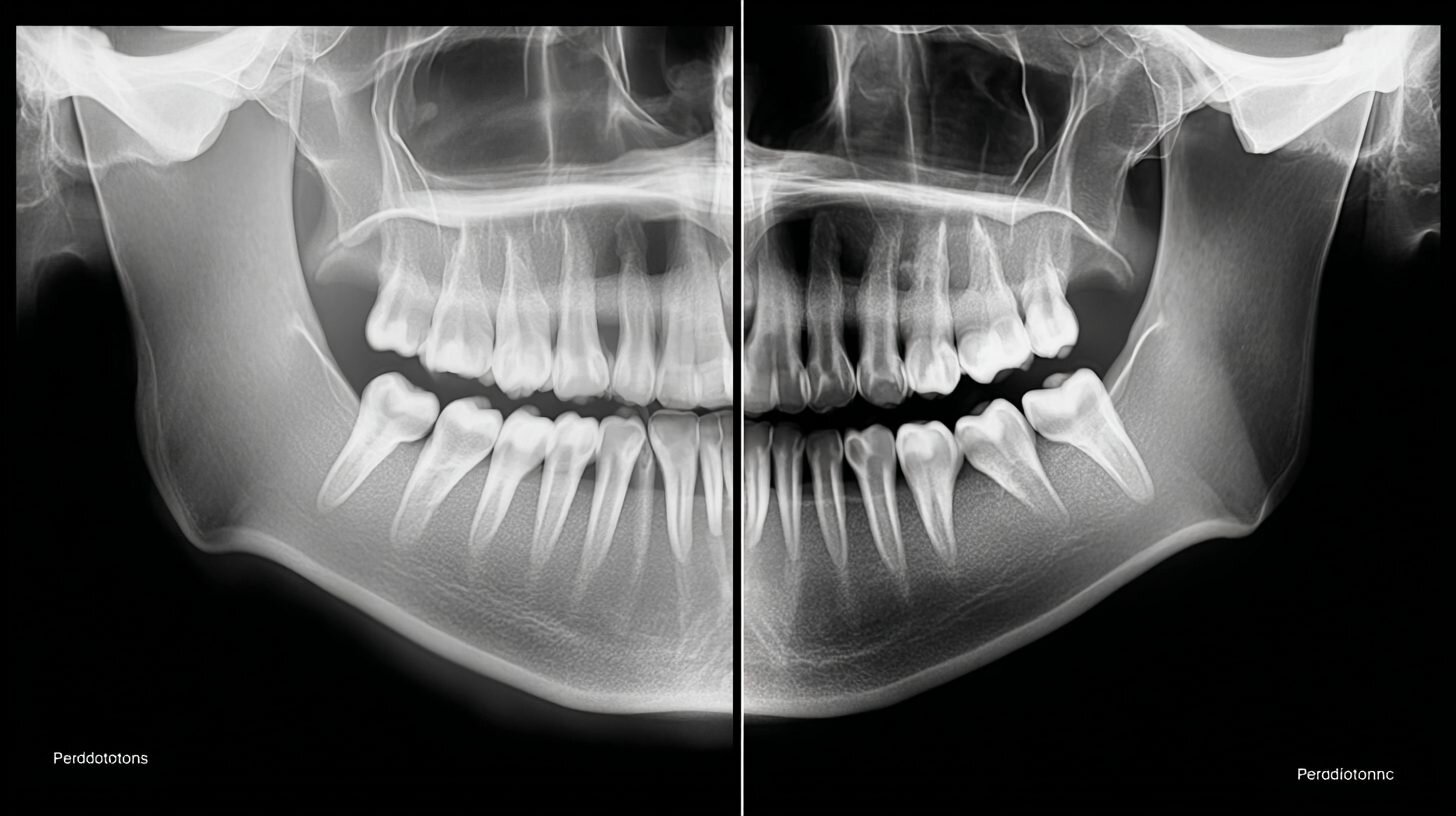

Сравнение пародонтита и пародонтоза на рентгенеРентгеновские снимки, иллюстрирующие различия в поражении кости при двух заболеваниях.

Понимание этих отличий позволяет пациентам своевременно обращаться за помощью, минимизируя риски. В контексте российского рынка услуг, где доступны как государственные, так и частные клиники, выбор зависит от доступности и квалификации персонала.

Различия между пародонтитом и пародонтозом определяются этиологией и клинической картиной. Пародонтит носит воспалительный характер с инфекционным компонентом, в то время как пародонтоз — дистрофический, связанный с системными нарушениями. Общие черты включают потерю опоры зуба, но пути развития отличаются: в первом случае — вертикальная деструкция кости, во втором — горизонтальная.

Ключевым отличием служит наличие воспаления в пародонтите против его отсутствия в пародонтозе, что влияет на выбор лечебных стратегий.